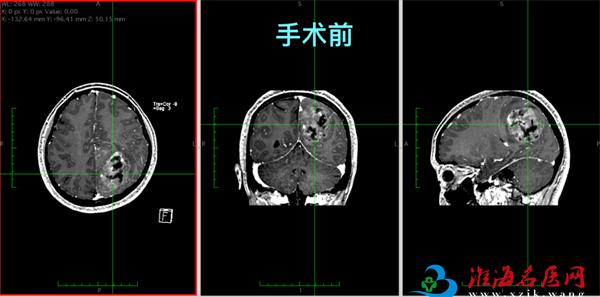

近日,徐州市中心医院神经外科董楠博士团队成功完成一例高风险脑肿瘤切除术。患者术后复查显示,肿瘤实现肉眼全切,颅内重要血管保存完好,手术区域无渗血,患者肢体活动障碍得到明显缓解,目前已康复出院。

进一步检查发现,肿瘤直径达7厘米,体积接近成人拳头,位置特殊——它长在了大脑的“运动中枢”中央前回附近。

术后患者行颅脑MRI复查,结果显示肿瘤实现肉眼全切,中央前回区域得到良好保护,上矢状窦等重要血管结构保存完好,手术区域未见明确渗血或血肿形成。患者术前存在的下肢活动障碍得到有效缓解,力量恢复正常,目前已康复出院,准备接受后续治疗。